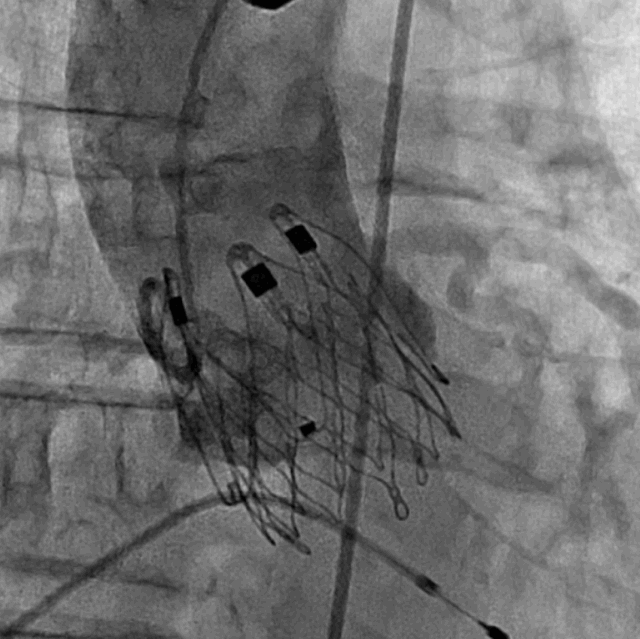

术后DSA影像图

手术采用经心尖入路,对患者进行全麻后,在左侧心尖处微创手术切口仅3-4cm,在DSA及超声引导下植入JS-TAVI29#牛心包瓣膜,手术顺利完成。术前升主动脉根部测压86/47mmHg,左室压91/9mmHg,术后升主动脉根部测压87/49mmHg,左室压98/10mmHg。从导入器械到完成瓣膜置入,耗时9分钟。术后即刻主动脉瓣返流程度由术前大量返流转为消失,术后测得跨瓣峰值流速1.8m/s,平均跨瓣压差6mmHg,峰值跨瓣压差12mmHg。